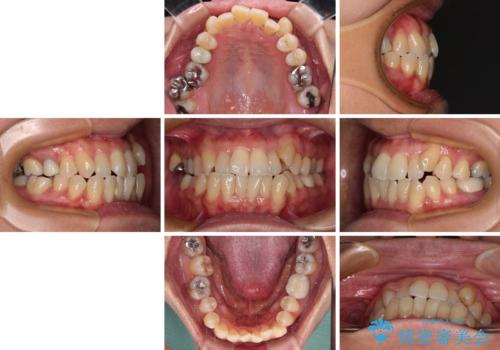

受け口と八重歯を改善 インビザライン矯正治療

- 前歯のデコボコや八重歯を治したいとのことで来院された患者様です。

受け口傾向の骨格であり、前歯はクロスバイトまたは切端咬合となっており、下顎を中心に歯列全体の後方移動を行い、IPR(歯と歯の間を削る)によってデコボコが解消するように設計し、インビザラインにより治療を行うこととしました。

受け口傾向のインビザライン矯正は比較的治療を行いやすいため、きれいに仕上げることができました。舌の突出癖が顕著であったため、改善のためのトレーニングをしっかりと行っていただきました。